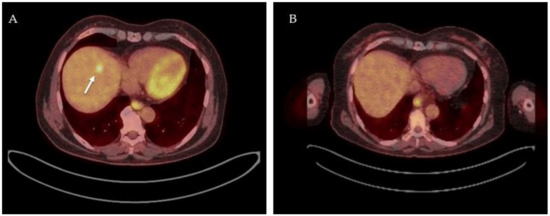

- Cornelis, F.; Sotirchos, V.; Violari, E.; Sofocleous, C.T.; Schoder, H.; Durack, J.C.; Siegelbaum, R.H.; Maybody, M.; Humm, J.; Solomon, S.B. 18F-FDG PET/CT Is an Immediate Imaging Biomarker of Treatment Success after Liver Metastasis Ablation. J. Nucl. Med. 2016, 57, 1052–1057. [Google Scholar] [CrossRef]

- Cornelis, F.H.; Petre, E.N.; Vakiani, E.; Klimstra, D.; Durack, J.C.; Gonen, M.; Osborne, J.; Solomon, S.B.; Sofocleous, C.T. Immediate Postablation 18F-FDG Injection and Corresponding SUV Are Surrogate Biomarkers of Local Tumor Progression After Thermal Ablation of Colorectal Carcinoma Liver Metastases. J. Nucl. Med. 2018, 59, 1360–1365. [Google Scholar] [CrossRef]